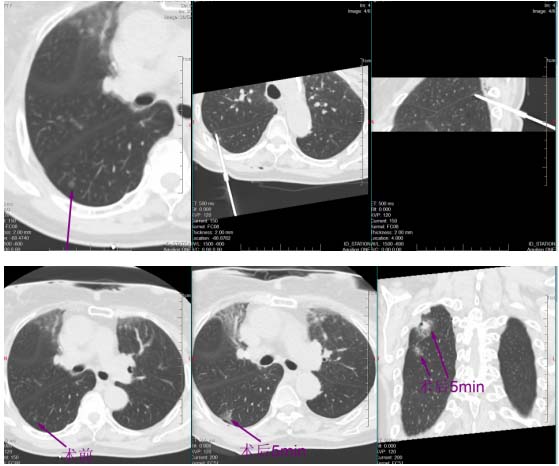

挑战随即开始。帕金森病导致黄女士身体不时微颤,这对需要毫米级稳定的穿刺是巨大干扰。于明川凝神屏息,双手稳如磐石,细微调整针道,在CT的实时引导下,消融针稳稳穿过8毫米的磨玻璃结节,精准停在胸膜前方3厘米处,完美避开胸膜危险区。“开始消融,30瓦一分钟!”随着指令下达,微波消融针开始加热,热量在结节处缓缓扩散,将病灶逐步凝固坏死。黄女士全程清醒,未感丝毫不适。

一分钟后,复查CT显示,结节被一圈磨玻璃密度影完整包裹,这意味着病灶已完全处于烧灼区内,第一枚结节消融成功!

稍后,于明川与冯文汉等团队成员密切配合,向难度更高的第二枚结节发起冲击。这枚结节藏在叶间裂与胸膜构成的狭小夹角内,可操作空间极小,如同在“夹缝中绣花”。按照术前预案,于明川放弃平行进针思路,采用由下而上的特殊进针方式,巧妙避开关键解剖结构。针尖精准抵达结节区域,经过反复测量确认安全后,30瓦功率持续消融一分钟。术中,黄女士的心率、血压始终平稳,未出现任何不良反应。术后CT扫描证实,结节被完全覆盖,烧灼区与叶间裂仅隔几毫米,这毫厘之间的精准,正是生命安全的坚实屏障。

一小时后,铅门再次打开。于明川将黄女士的儿女引至屏幕前,影像清晰地显示:两枚结节已被完全覆盖,消融范围边缘距离关键解剖结构仅存毫厘之差。“两个结节都顺利消融成功了,没有并发症,手术很成功!”话音落下,黄女士儿女心中悬了许久的大石终于落地。看着术后安然躺在病床上、面容平和的母亲,他们眼中盈满欣慰。

术后第二天,经过严密监护,黄女士顺利出院。如今,术后的随访显示,黄女士生活如常,当地复查CT提示结节已彻底消失,手术区域仅留下两条细线状疤痕。这场跨越三千公里的求医之旅,在北京大学首钢医院医疗团队的仁心仁术中画上圆满句号。